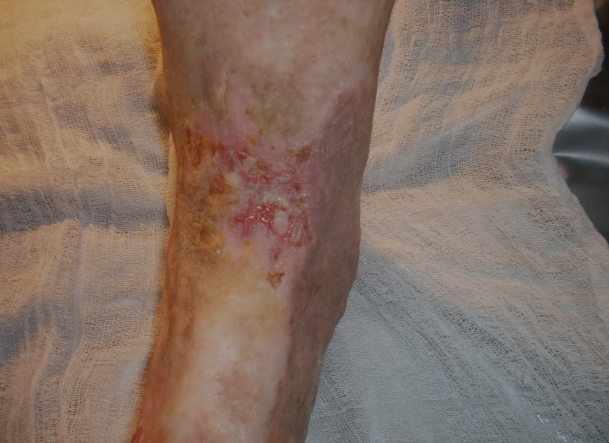

Chegando lá, deparou-se com muitos pacientes que eram portadores de lesões ulceradas crônicas nos membros inferiores, as Ulceras Varicosas.

Problema este que sua avó paterna carregou durante toda a sua vida. Durante toda a infância viu o sofrimento dela. Dores diariamente, levando também ao sofrimento de outros familiares. Dr. Gotardo nasceu, cresceu e formou-se em medicina e nunca teve um dia sem vê a avó sem que estivesse com o sofrimento do “machucado” das pernas.

Após os problemas políticos aos quais mencionamos ao ir clinicar em Minas Gerais encontrou o que faltava: Muitos pacientes com o problema e muito conhecimento popular que somado aos conhecimentos científicos que tinha chegou-se a uma conduta que podemos chamar de CONDUTA ÚNICA, para o tratamento destas lesões, que independente do tratamento ou tratamentos já realizados e o tempo do inicio das lesões. O tratamento realizado com esta CONDUTA ÚNICA em apenas 15 ou 30 dias, cura-se as lesões Varicosas “pele-a-pele”. Mesmo pacientes com fatores complicativos como o caso de “Pés Diabéticos”.

ANTES E DEPOIS

Confira os resultados reais de nossos pacientes